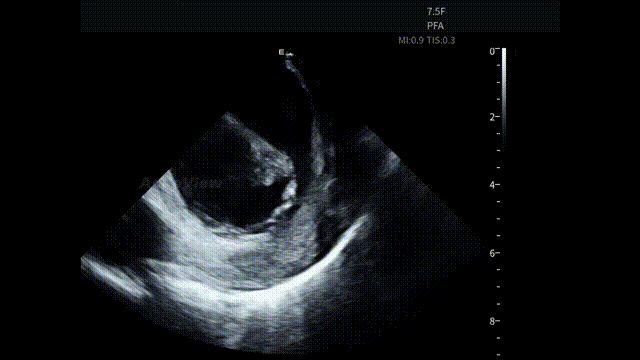

手术结束前,ICE 再次跨瓣扫查心包区域,确认积液未见进展,为手术安全形成完整影像闭环。

术后心包筛查-积液无变化

SVC